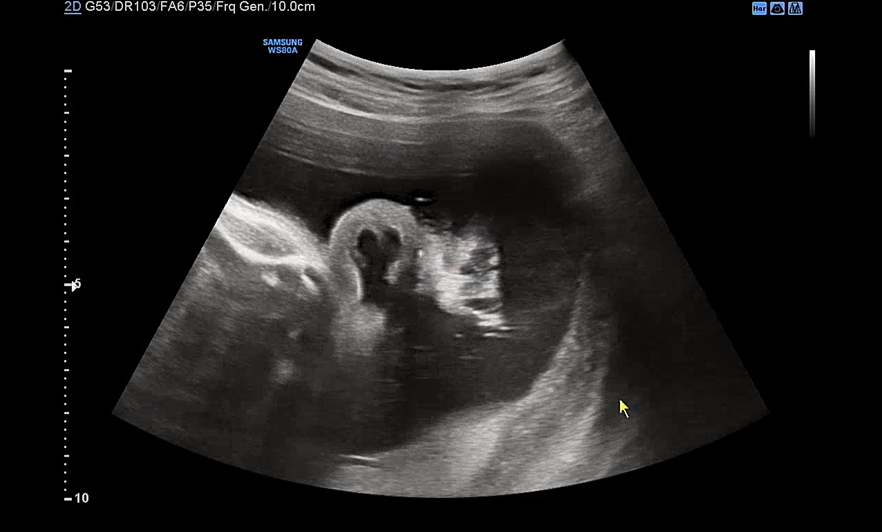

이 날 우리 아기는 배에 얼굴을 파묻고선 얼굴을 보여주지 않았다. 아니 지난주에는 그렇게 잘 보여주더니 이번엔 얼굴을 돌릴 기미가 1도 안보였다. 요건 얼굴을 돌린 상태에서 귀만 살짝 보여준 모습.

눈이 살짝살짝 보이다가도 푹 다시 파묻어버리는. 다음 검사때에는 초코우유를 먹여야겠다며 남편이 어찌나 아쉬워하던지 모르겠다. 초음파 검사를 마치면 항상 원장님께서 궁금한 거 없냐고 여쭤보시는데 다른 임산부들은 뭘 물어볼까? 이제 운동을 조금 늘려도 되냐고 여쭤봤는데 무리되지 않는 선에선 괜찮다고 하셨다. 아주 막달이 아니고선 운동은 크게 권장되지 않는 느낌이다. 아기도 너무 잘 자라고 있고 내 컨디션도 너무 좋아 별로 물어볼 게 없었다. 사실 이 날 백일해 주사를 접종하기로 했는데 백신이 떨어져서 접종을 하지 못했다. 34주 전까지는 접종이 권장되는데 원장님께서 소아과나 정형외과에 물량이 있을 수 있으니 가까운 곳으로 전화를 해보라고 하셨다. 일단 2주 뒤 진료라서 그때 병원을 와보고 백일해 주사가 또 없으면 가까운 병원에 전화를 돌려보기로 했다. 이제 30주가 되니 출산용품 리스트에서 남은 물건들도 모조리 다 구입하고 빨래도 시작해야 한다. 엄청 일찍부터 이것저것 알아보고 준비한 거 같은데 한도 끝도 없는 출산 준비. 시간이 점점 부족한 기분이다.